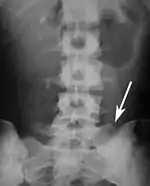

Block vertebrae of the cervical spine (vertebrae 4 and 5). Probably based on degenerative or inflammatory changes.

Several congenital block vertebrae in the transition from the thoracic to the lumbar spine and hemivertebrae.

Congenital block vertebra in the lumbar spine (partial vertebrae 3 and 4). The rear portion of the disc still exists.